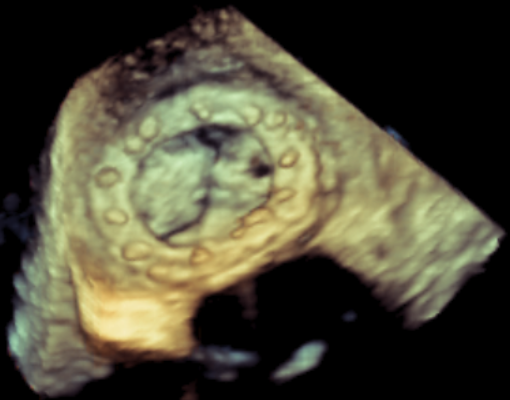

患者,男,70岁,于1月前无明显诱因下出现活动后胸闷,步行100米后出现气促伴双下肢乏力,无胸痛、发热、头晕头痛、发热畏寒、恶心呕吐及咳嗽等不适。患者于7年前行二尖瓣生物瓣置换术(Edwards Perimount 27#)。术前心脏超声提示:二尖瓣生物瓣置换术后:生物瓣重度狭窄(有效瓣口面积0.58cm²,MPG=12mmHg);左房增大(57mm)左室增大(舒张末前后径73mm),左室壁静息状态下运动弥漫性减弱,左室收缩功能明显减低(EF=29%,Simpson法);轻度肺动脉高压;术前心功能IV级。

原生物瓣少量反流

过瓣流增快,呈“五彩状”